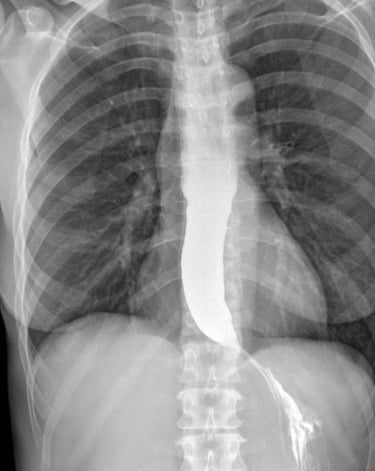

Il paziente ingerisce un liquido contenente solfato di bario (radiopaco), che riveste le pareti esofagee e permette di visualizzarle ai raggi X.

Si eseguono radiografie statiche e fluoroscopia dinamica per osservare il passaggio del contrasto attraverso l’esofago fino allo stomaco.

Si valuta il tono dello sfintere esofageo inferiore (LES) e l'eventuale reflusso del contrasto verso l’esofago.

📌 Reflusso gastroesofageo (GERD) → Visualizzazione del contrasto che risale dallo stomaco nell’esofago.

📌 Acalasia → Dilatazione dell’esofago con segno a becco di uccello.